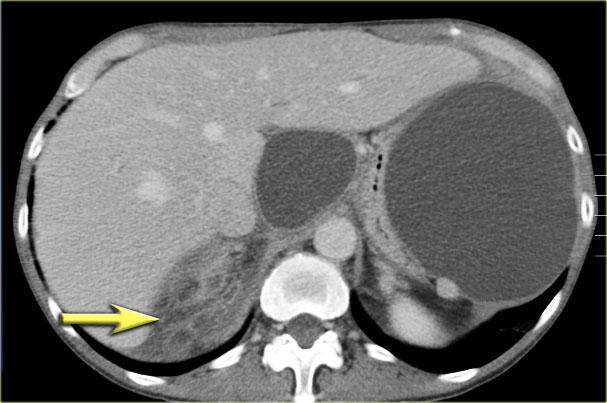

Một ví dụ khác về u nang tuyến thanh dịch (Hình).

Hình ảnh sau tiêm thuốc cản quang bên phải cho thấy tổn thương giảm tỷ trọng với vôi hóa trung tâm ở thân tụy và ngấm thuốc nhẹ của các vách ngăn.

Lưu ý rằng trên CT rất khó nhận ra bản chất dạng nang của các tổn thương này và có thể nhầm lẫn với ung thư biểu mô tuyến tụy.

MRI sẽ dễ dàng thể hiện bản chất dạng nang của các tổn thương này (hình).

Chuỗi xung T2W với xóa mỡ (fatsat) thể hiện rõ tổn thương tăng tín hiệu dạng thùy múi với sẹo trung tâm, đây là hình ảnh đặc trưng của SCN.